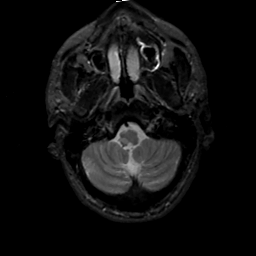

MR Study #2, February 17, 1991 -- Slice #6